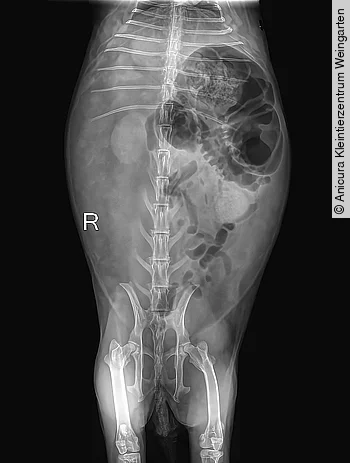

Röntgenuntersuchung

Es wurden am unsedierten Patienten jeweils Röntgenaufnahmen in latero-lateraler und ventro-dorsaler Projektion angefertigt, dabei stellte sich der Magen-Darm-Trakt inhomogen und mit kleinen Luftblasen durchsetzt dar. Der Magen zeigte einen geringgradigen Füllungsstand ohne Gasansammlung; sowohl Pylorus als auch Dünndarm wiesen keine pathologischen Veränderungen auf. Das Zäkum war hochgradig dilatiert und im linken Abdomen positioniert. Leber, Milz und Nieren lagen in ihrer normalen anatomischen Position und waren ohne besonderen Befund.

An der linken Seite des Inguinalbereichs wurde eine hypoechogene, runde Struktur mit ca. 1,5 × 2 cm gefunden, ein eindeutiger Hinweis für eine Magen-Darm-Obstruktion bestand nicht ([Abb. 1]). Anhand des Röntgenbefundes wurde eine Stase bzw. Hypomotilität des Zäkums vermutet. Wichtige Differenzialdiagnosen bei diesem Befund sind Dysbiose und mukoide Enteropathie. Der Thoraxbereich zeigte keine Auffälligkeiten.